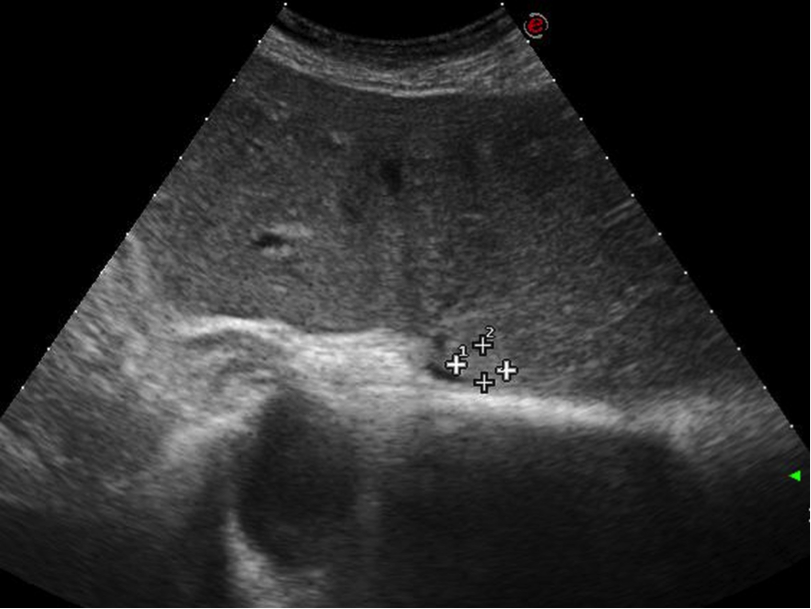

Un paziente con una metastasi al fegato di 8 mm nel segmento I particolarmente vicino al pericardio è stato sottoposto a Termoablazioen con EchoLaser. La lesione è stata ablata completamente senza nessuna complicazione legata alla struttura critica vicina come il versamento pericardico.

Immagine Ecografica prima del trattamento